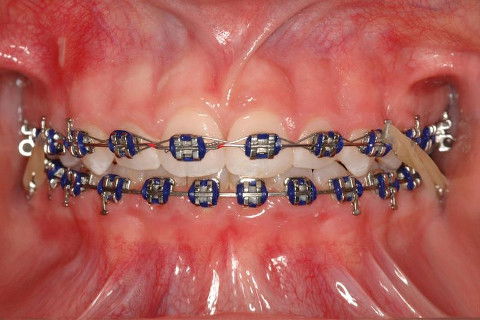

INSTALAÇÃO APARELHO FIXO SUPERIOR E INFERIRO (ROTH)

CLASSE I

CLASSE II

FINALIZAÇÃO; ELÁSTICO DE CLASSE II DUPLO.

FINALIZAÇÃO; ELÁSTICO DE CLASSE II SIMPLES.